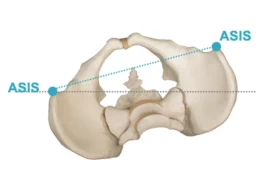

اعوجاج العمود الفقري هو انحناء غير طبيعي يحدث في الجانب، أي يمينًا أو يسارًا، وغالبًا ما يصاحبه دوران في الفقرات. لذلك، لا يكون مجرد انحناء بسيط، بل حالة ثلاثية الأبعاد تؤثر على شكل الجسم بالكامل.

📌 من أهم علامات اعوجاج العمود الفقري:

- ميل الكتف إلى جهة واحدة

- بروز أحد جانبي القفص الصدري

- عدم تساوي مستوى الخصر

- انحراف واضح في شكل الظهر

👉 بالإضافة إلى ذلك، قد يؤثر الاعوجاج على التوازن ووضعية الجسم، وأحيانًا على التنفس في الحالات الشديدة.